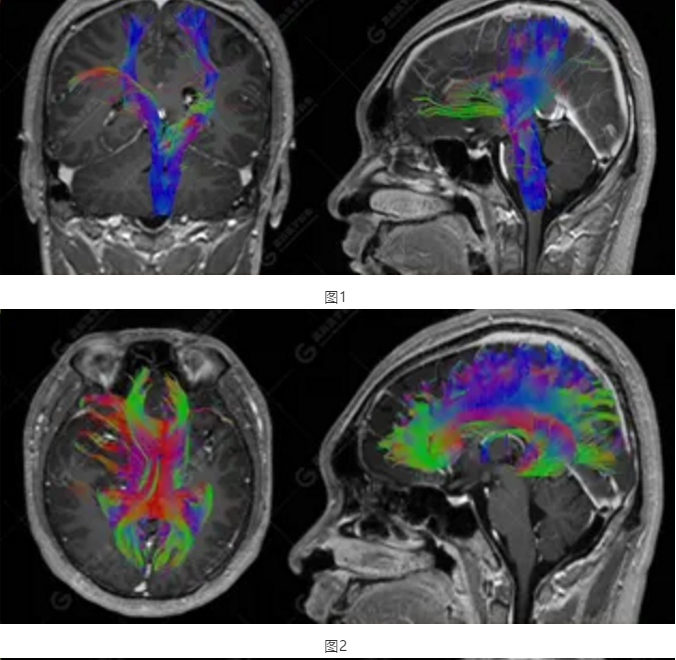

以上為DTI成像,圖1為皮質(zhì)脊髓束,圖2為胼胝體束,圖3為扣帶回束,圖4為額枕束。DTI成像示右側(cè)額枕束前部明顯受壓、部分未見顯示;胼胝體束、雙側(cè)扣帶束、皮質(zhì)脊髓束及左側(cè)額枕束形態(tài)可,纖維束未見明顯破壞,未見明顯稀疏減少。